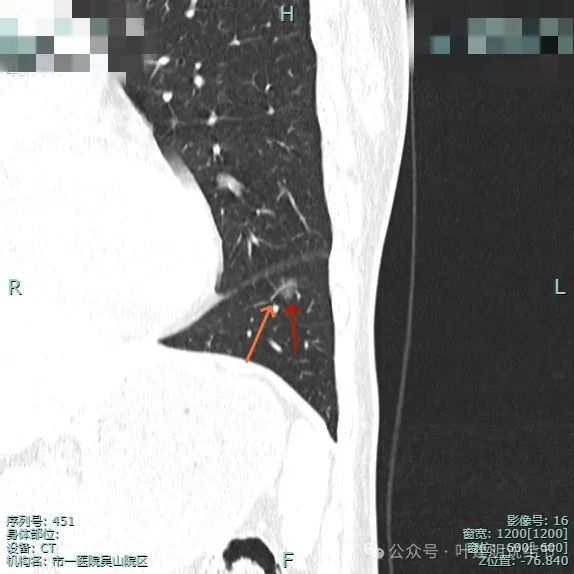

靶重建图像:

病灶边缘毛糙,微小血管进入明显。灶内密度略不均。

血管进入与穿行明显,而且在病灶内有发出血管分支,病灶表面不平,有毛刺征。

小血管进入明显,边缘有毛刺征,整体轮廓与边界清。

血管进入,灶内小空泡征,邻近细支气管有扩张,表面有细毛刺。

多处血管征,表面毛糙,轮廓清楚,有不太典型的血管弯征,灶内密度稍不均。

叶间胸膜牵拉较平扫上明显,血管进入也明显,整体轮廓清。

灶内有点状偏高密度成分,内部密度稍显杂乱;叶间胸腊牵拉,整体轮廓清。

多支血管进入,而且灶内的血管显得较病灶外略粗与略模糊,叶间胸膜牵拉是有的,力量不强。